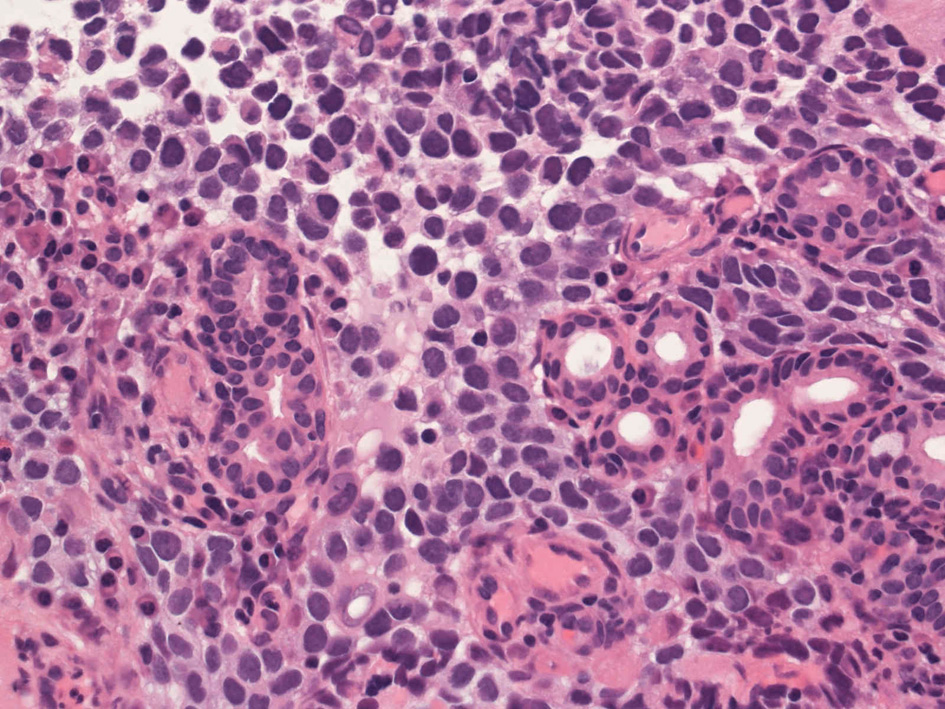

Alveolar rhabdomyosarcoma

Alveolar rhabdomyosaroma

Undifferentiated small round cell tumors of the sinonasal tract

rhabdomyosarcoma 横紋筋肉腫

40歳女性 鼻粘膜腫瘤

右頸部のしこりを自覚。近医MRIで頸部多発リンパ節腫大あり当院を紹介される。右顎下, 右鎖骨上窩にも多数のリンパ節を触れる。穿刺細胞診ではcarcinoma疑い。右鼻腔, 上顎洞にも腫瘤が認められリンパ節腫大との関係を調べるために鼻腔腫瘤の生検が行われる。

病理組織所見